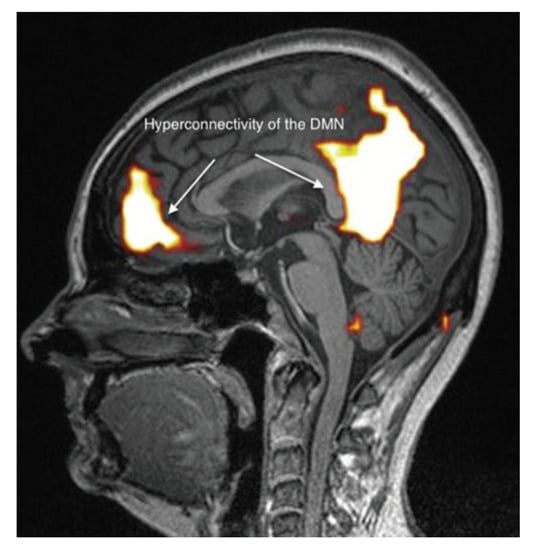

It appears, however, that these brain abnormalities are not restricted to the limbic system and the thalamus, since, by using TDU as indicated above, we showed that, in EHS and/or MCS patients, BBF in the middle cerebral arteries may be abnormal. Moreover, by using functional MRI (fMRI) in EHS patients exposed chronically to extremely low-frequency (ELF) radiation, regional BBF changes were also reported by Heuser and Heuser, but mainly in the frontal lobes, as an abnormal default mode network (DMN) (particularly as hyper-connectivity of this DMN), in association with a decrease in cerebral BBF and metabolic processes in the two so far individualized fragment hyper-connected components []. For example, in Figure 4, abnormal DMN is represented with fragmented hyper-connectivity of the anterior component and posterior component, which may lead to decreased BBF and/or metabolism in the bi-frontal lobes.

Figure 4. Abnormal functional MRI brain scan in patients complaining of EHS after long-term exposure to EMF, according to Reference [].